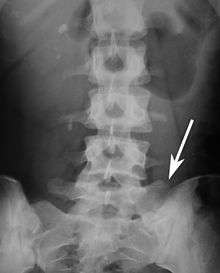

Sacralization of the fifth lumbar vertebra (or sacralization) is a congenital anomaly, in which the transverse process of the last lumbar vertebra (L5) fuses to the sacrum on one side or both, or to ilium, or both. These anomalies are observed at about 3.5 percent of people, and it is usually bilateral but can be unilateral or incomplete (ipsilateral or contralateral rudimentary facets) as well. Although sacralization may be a cause of low back pain, it is asymptomatic in many cases (especially bilateral type). Low back pain in these cases most likely occurs due to chronic faulty biomechanics. In sacralization, the L5-S1 intervertebral disc may be thin and narrow. This abnormality is found by X-ray.